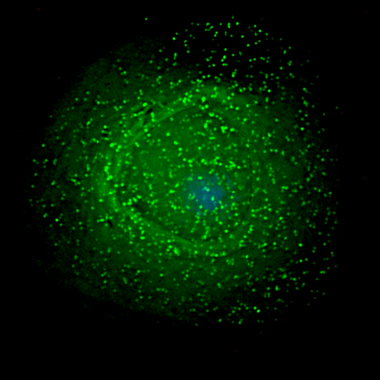

VIH penetrando en la superficie de un macrófago infectado. / Wikipedia